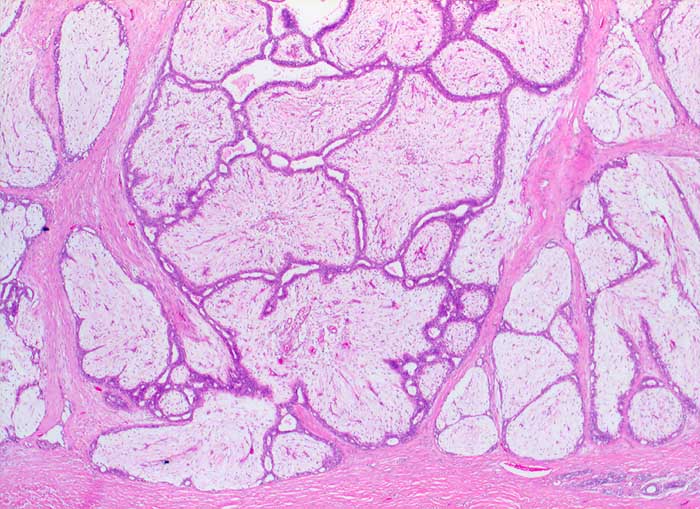

Grosse Mengen epithelialer Zellen, bipolarer Nacktkerne (Myofibroblasten und Fibrozyten) und scharf begrenzte Stromafragmente charakterisieren das Fibroadenom zytologisch. Aspirate von stark fibrosierten Fibroadenomen können auch zellarm sein. Einseitig von Epithel bedeckte Bindegewebsfragmente sprechen für ein Fibroadenom. Durch die Aspiration wird die epitheliale Innenauskleidung mit ihren Verzweigungen aus dem Gangsystem gelöst. Die Epithelverbände sind beim intrakanalikulären Fibroadenom flach und erscheinen beim perikanalikulären Fibroadenom T-, Y-, finger- oder hirschgeweihförmig. Die Kerne sind wenig grösser als die Kerne normaler duktaler Epithelien und messen meist weniger als zwei Erythrozytendurchmesser. Da es sich bei Fibroadenomen um proliferierende Läsionen handelt können die Epithelzellen Zeichen der Aktivierung zeigen in Form einer mässig ausgeprägten Pleomorphie, prominenten Nukleolen, und gelegentlichen Mitosen.

Das erste Beispiel zeigt ein intrakanalikuläres, das zweite Beispiel ein perikanalikuläres Fibroadenom mit stark verzweigten Zellverbänden. Das dritte Beispiel zeigt die Zytomorphologie eines Fibroadenoms mit stark aktivierten Zellen.